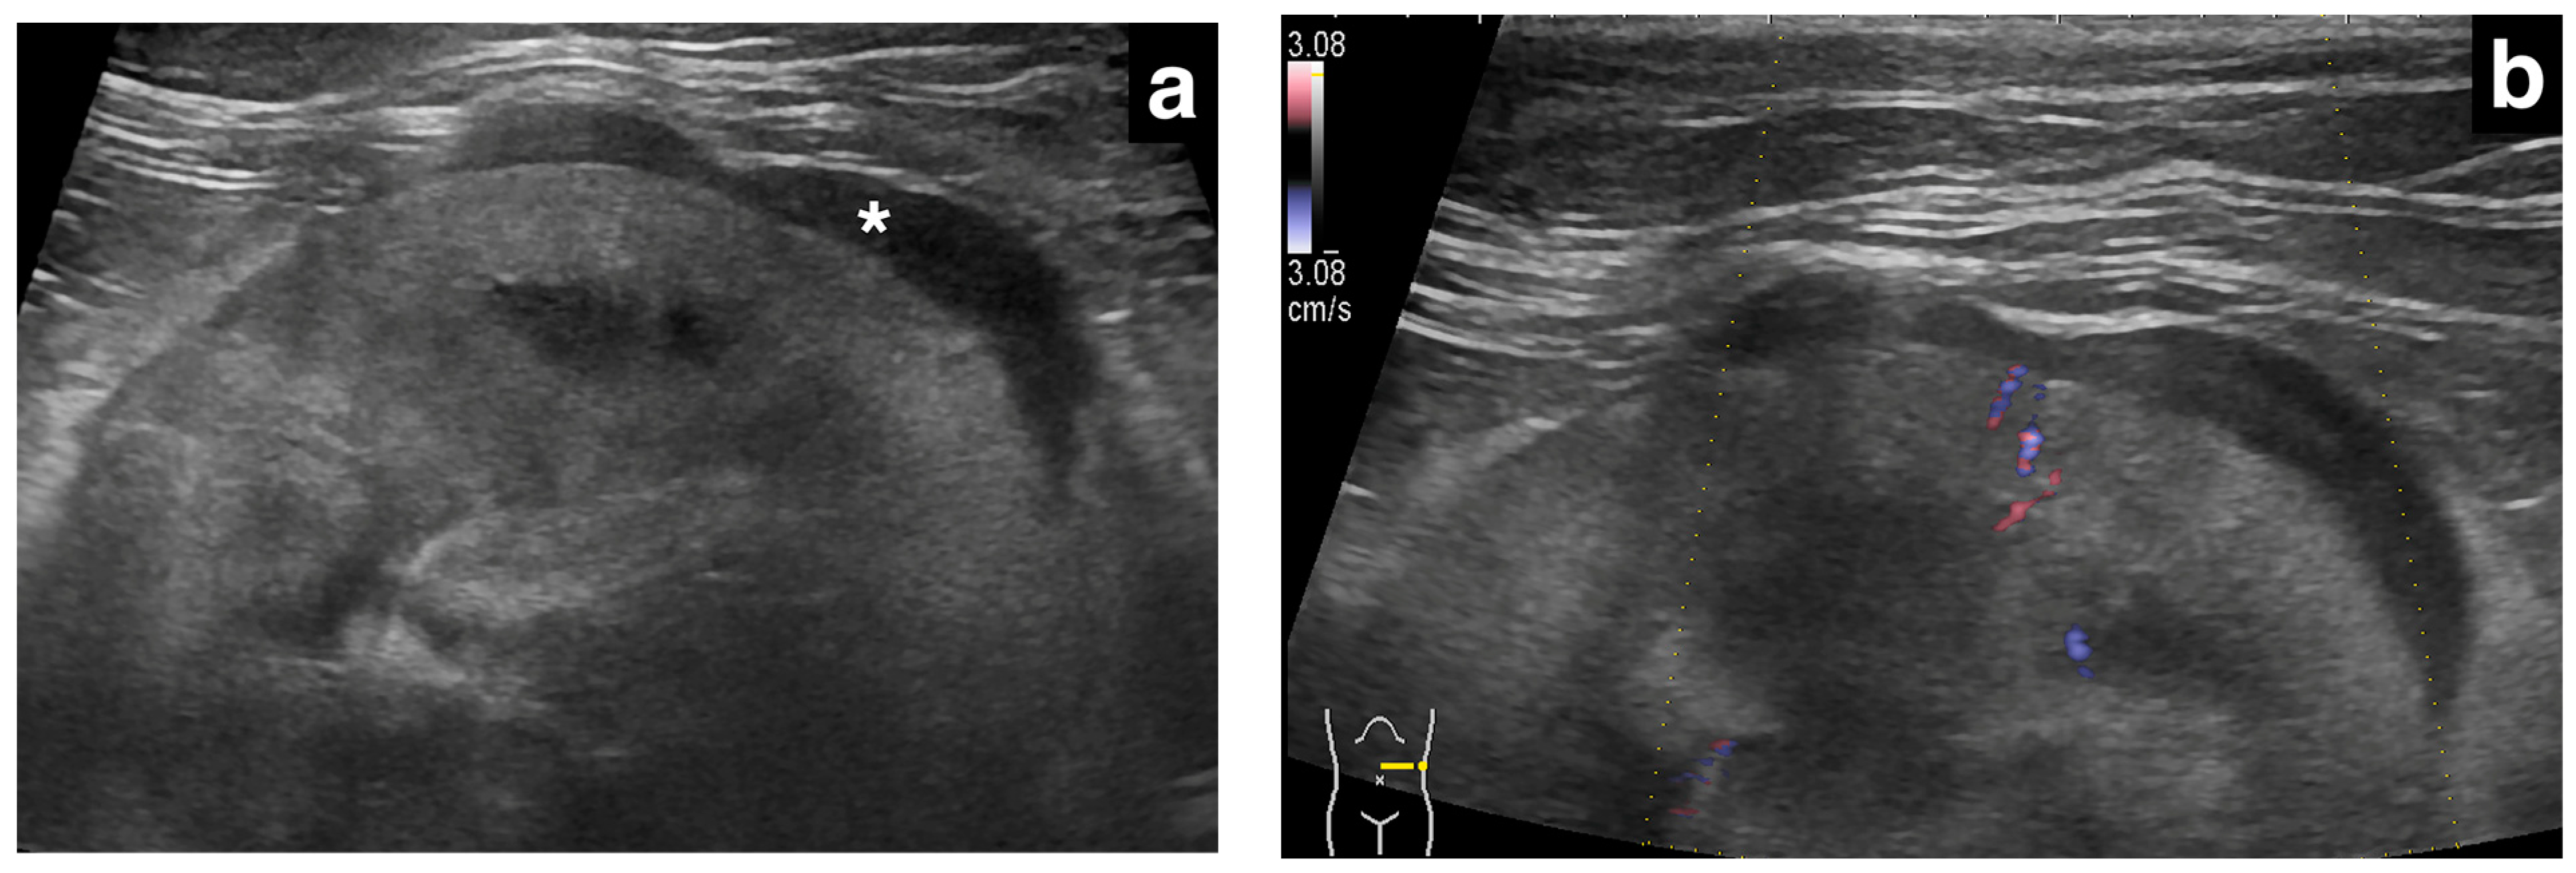

In our study population, renal subcapsular thickening was observed bilaterally in three cats, unilaterally in the left kidney in two cats, and in the right kidney in one cat, for a total of nine kidneys from six cats. For the image evaluation, 1–15 images and 0–2 videos were available per kidney. The ultrasonographic findings and diagnoses are listed in Table 1. The ultrasonographic evaluation showed that the maximum thickness of the subcapsular thickening ranged from 1.0 to 13.2 mm (median 3.0 mm), with one kidney with primary renal carcinoma showing a markedly thickened lesion (13.2 mm), while the others (metastatic carcinoma) were less than 5 mm in thickness. The distribution of the subcapsular thickening lesion was focal in eight kidneys (8/9; Figure 1, all metastatic carcinomas) and circumferential in a single kidney (1/9; Figure 2, primary renal carcinoma). In all eight metastatic carcinomas, the kidney showed focal, homogeneous, and hypoechoic subcapsular thickening (Figure 1). In a primary renal carcinoma kidney with circumferential thickening, the subcapsular thickening was heterogeneously mixed isoechoic to hypoechoic relative to the renal cortex (Figure 2).

Furthermore, a previous report on ultrasonographic renal hypoechoic subcapsular thickening included two cats with presumed primary renal neoplasia, specifically undifferentiated malignant neoplasia and renal anaplastic carcinoma [1]. These cats showed hypoechoic subcapsular thickening, but the report did not provide ultrasonographic images or a detailed description of these findings in cats with primary renal neoplasia [1]. In the present study, we observed subcapsular thickening in a single case of primary renal neoplasia in a cat, which showed heterogeneously mixed isoechoic to hypoechogenicity (Figure 2). Although this finding was based on only one case, our results suggest that the subcapsular thickening caused by primary renal neoplasia may not always show a diffuse hypoechoic appearance.

Figure 2. Ultrasonographic image of a kidney with primary renal carcinoma (case 6, left kidney). A thick, circumferential, heterogeneously mixed isoechoic to hypoechoic subcapsular thickening (double-headed arrow) was present. The renal cortical and the renal capsular margins were irregular. Note the diffuse, markedly hyperechogenic renal cortex.